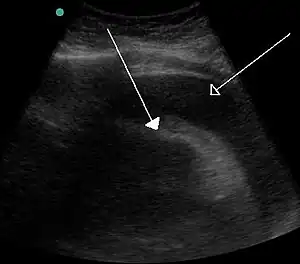

Bladder tamponade is obstruction of the urinary bladder outlet due to heavy blood clot formation within it.[3] It generally requires surgery.[3] Such heavy bleeding is usually due to bladder cancer.[4]